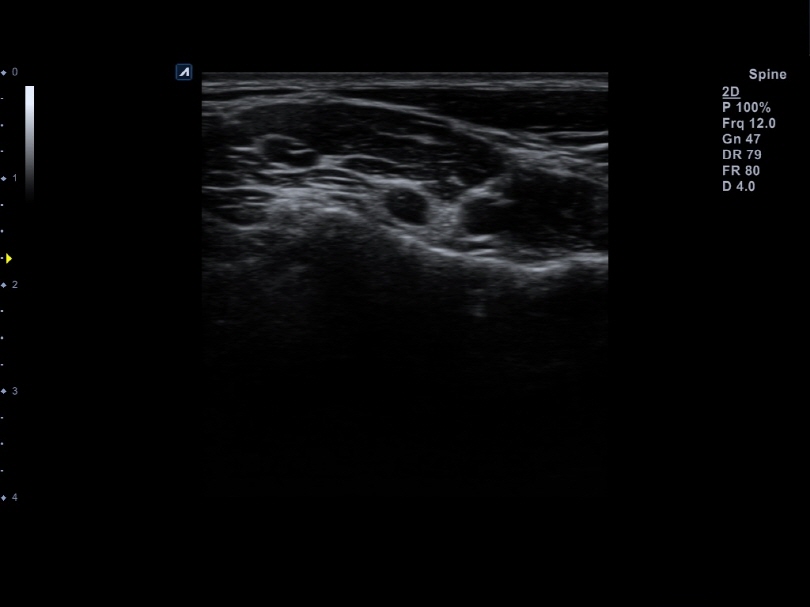

L8-17H

High density linear transducer(8-17MHz)

Application:

Breast, EM, MSK, Vascular, Small Parts

L3-12H

High density linear transducer (3-12MHz)

Application:

Breast, EM, MSK, Vascular, Small Parts

L3-12HWD

High density wide footprint linear transducer (3-12MHz)

Application:

Breast, EM, MSK, Vascular, Small Parts, Appendix

L3-12T

Linear transducer (3-12MHz)

Application:

Breast, EM, MSK, Vascular, Small Parts, Appendix